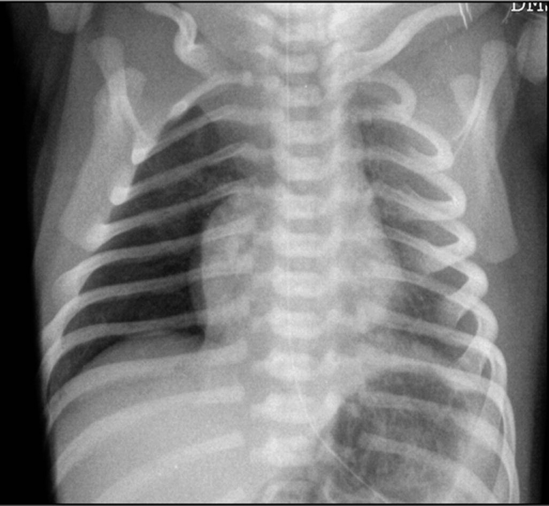

Xray findings

- Hyperinflation,

- Consolidation,

- Patchy infiltrates

- If severe, air leak and pneumomediastinum may occur

- Lines going from inside to outside

The infant has been on a ventilator for about 6 hours when you are called to the bedside for sudden decompensation with decreased saturations as low as 30%, bradycardia, and absent breath sounds on the right.

- What do you expect happened? pneumothorax

- What is your immediate action? right needle decompression 2nd intercostal mid clavical

well demarcated right lung pnumothorax - pushed

effusion pulls